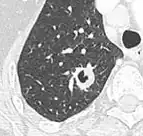

- Margin morphology: a spiculated margin is a risk factor for cancer.[8] Benign causes tend to have a well defined border, whereas lobulated lesions or those with an irregular margin extending into the neighbouring tissue tend to be malignant.[10] In particular, spiculations are highly predictive of malignancy with a positive predictive value up to 90%.[9] Also, a "notch sign", which is an abrupt indentation of the nodule, increases the risk of cancer, but may also be found in granulomatous diseases.[9]

-

subpleural nodule.[9] -

Round well-delineated solid lung nodule with smooth border.[9] -

Lobulated nodule.[9] -

Spiculated lung nodule.[9] -

A "notch sign".[9] -

A triangular perifissural node can be diagnosed as a benign lymph node.[9]